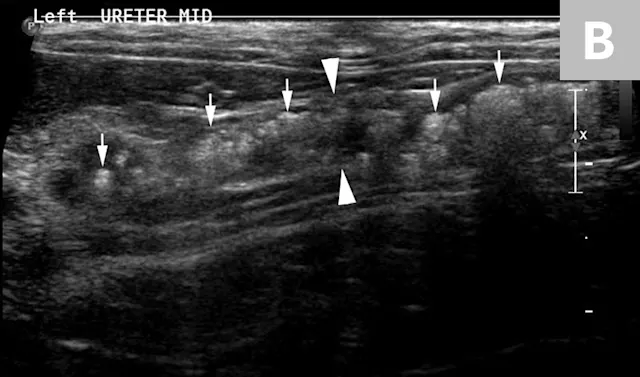

The obstruction can be located at any point of the ureter and can vary in severity. Normal ureters are typically not seen on ultrasonography due to their small size. The easiest way to locate a dilated ureter is to trace the ureter from the renal pelvis. In most cases, the ureter is dilated proximal to the site of an obstruction and tapers to a more normal appearance distal to the site of obstruction. Imaging can also reveal retroperitoneal effusion which can result from ureteritis and possible urine leakage.

Clinical signs associated with ureteral calculi may range from chronic non-specific signs to acute or chronic renal failure. The presence of hydronephrosis can be highly suggestive of a ureteral obstruction (Figure 6).